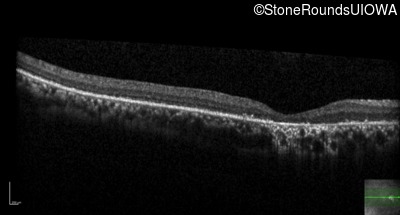

The clinical features supporting the diagnosis of Bardet Biedl syndrome in this patient include: bone-spicule-like pigmentation, narrowed arterioles and macular atrophy on ophthalmoscopy; photoreceptor loss on OCT; ulnar polydactyly, obesity, abnormal cognition, hypertension; and, normally sighted parents.